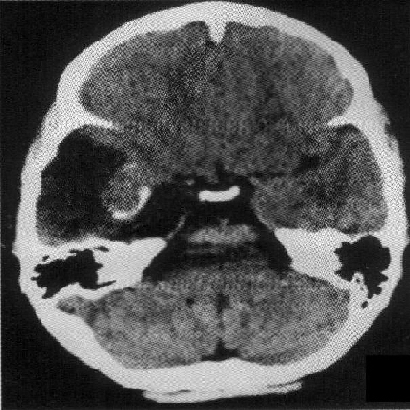

标题: PED1818:男,13岁。头痛5天,复视、呕吐3天。体检:神经生 [打印本页]

标题: PED1818:男,13岁。头痛5天,复视、呕吐3天。体检:神经生

右中颅窝见囊性占位影,其中央见块状高密度影,高密度块后后缘见条状钙化?前部与殘存颞叶皮质相连,临近骨质无异常,病灶囊变区呈长t1长t信号,实性区呈中等信号,增强(最后两副是增强t1像吧)有明显强化,实性块影上部尚见鸟嘴状影(比较像脑膜尾),考虑右中颅窝脑膜瘤可能性大,不排除室管膜瘤,畸胎瘤等

病理:囊性脑膜瘤